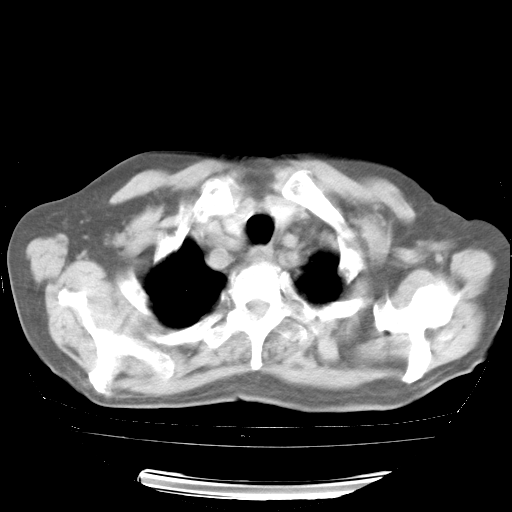

4月28日肺部CT——再次出现类似去年5月9日——透光度降低,“间质性”改变。